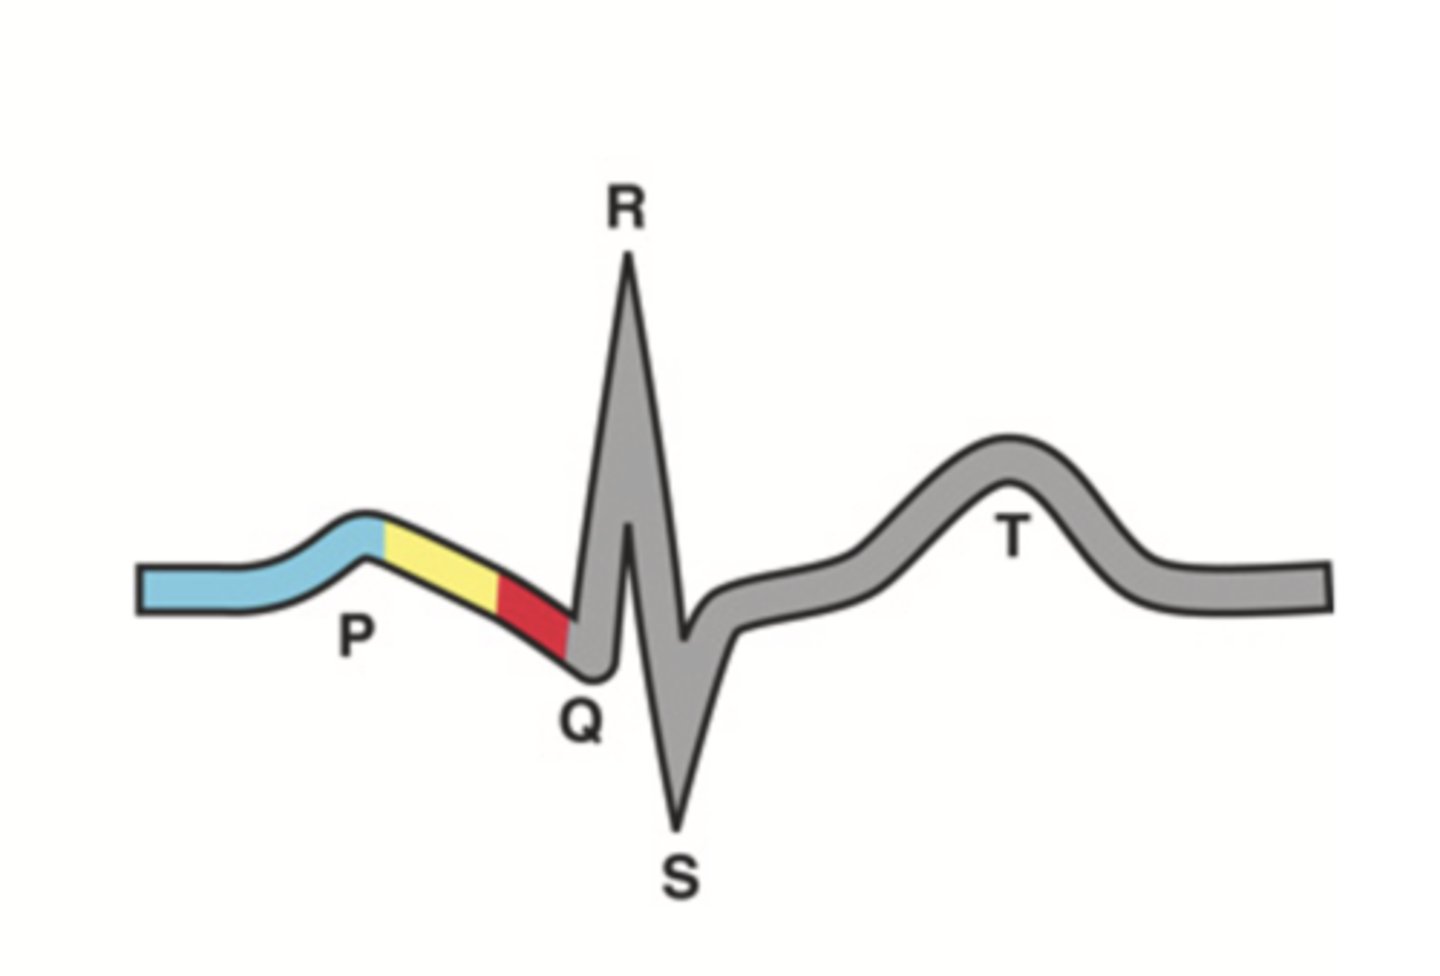

4 Parts of the Heart's Conduction System

- Sinoatrial (SA) node

- Atrioventricular (AV) node

- Bundle of His

- Purkinje fibers

Sinoatrial (SA) Node

Pacemaker of the heart conduction system, located at the right atrium (light blue)

Atrioventricular (AV) Node

The part that relays electrical impulses from atria into the bundle of his in the heart's conduction system; delayed slightly (yellow)

Bundle of His

Part of the heart's conduction system that transmits the cardiac impulse from the atrioventricular node to the purkinje fibers (red)

Purkinje Fibers

Fibers in the ventricles that transmit impulses to the right and left ventricles, causing them to contract

ECG Waves

- P wave

- P-R interval

- QRS complex

- Q-T interval

- T wave

P Wave

Atrial depolarization

P-R Interval

Atrial contraction

QRS Complex

Ventricular depolarization

Q-T Interval

Ventricular contraction

T Wave

Repolarization of ventricles